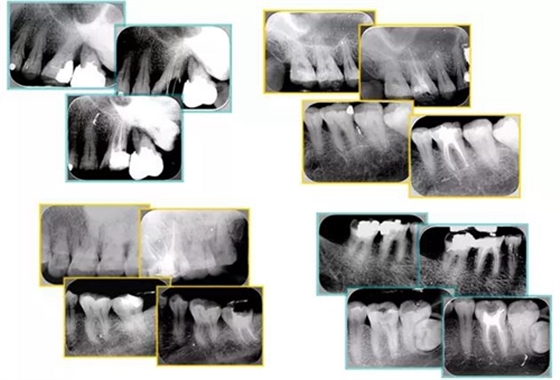

共有 4 張 X 線片,分別是術(shù)前、診斷絲 、主牙膠尖確認(rèn)、術(shù)后。

( 1 )術(shù)前:術(shù)前 X 線片用來(lái)了解牙齒的大概情況。術(shù)前預(yù)期為多根牙時(shí) X 線片應(yīng)偏頭拍攝。

( 2 )診斷絲:根據(jù)術(shù)前 X 線片進(jìn)行開(kāi)髓、根管的初步預(yù)備后,需要插入診斷絲,用來(lái)指示工作器械位置。常用 10 號(hào)或 15 號(hào)擴(kuò)大器作為診斷絲插入牙髓腔。

( 3 )主牙膠尖確認(rèn):通過(guò)術(shù)前預(yù)期和診斷絲診斷,明確工作長(zhǎng)度、牙根走向,進(jìn)行根管預(yù)備。之后應(yīng)進(jìn)行主牙膠尖(中銼)確認(rèn),已明確根管是否適合充填。

( 4 )術(shù)后:觀察治療效果。

6. 術(shù)后 X 線片

術(shù)后 X 線片用來(lái)評(píng)定根管充填 長(zhǎng)度、致密度(管壁清晰、側(cè)枝)等指標(biāo)。

左圖為根管充填術(shù)后 X 線片。圖中可見(jiàn),根管充填較好。右下圖有白色小點(diǎn),為側(cè)方加壓導(dǎo)致糊劑擠出所致,表明根管充填比較致密。

多根牙時(shí)候需進(jìn)行偏移投照,正位投照無(wú)法說(shuō)明具體哪根牙根管充填效果。

如圖為塑化加根充處理后牙齒 X 線片。

常見(jiàn)有修復(fù)性鈣化和增齡性鈣化。下面為根管鈣化 X 線片。

下圖為器械折斷的 X 線片。箭頭處示折斷器械。